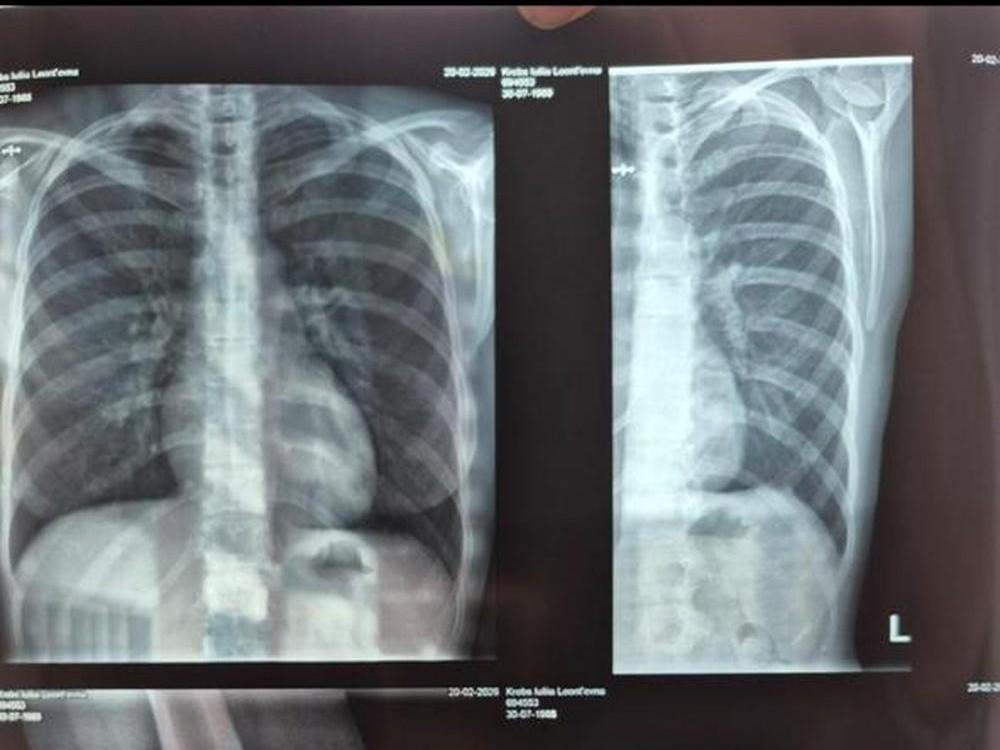

Врачи диагностировали перелом 11-го ребра у пострадавшей.

Медицинское обследование выявило у женщины тупую травму грудной клетки, перелом 11-го ребра без смещения, ушибленную рану и гематому локтевого сустава. После этого она подала заявления в полицию и прокуратуру.